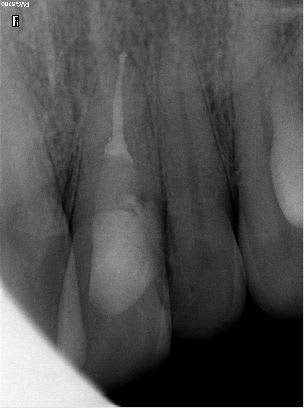

tu n'es pas seul pxav :D

Le mec à bien morflé (coté palatin ça pique) mais la dent est encore là.....

pour le moment... Je le motive pour le davier cet été, au cas où.

pour l'obturation "coffrage" interne avec un cône de gutta, coffrage externe avec un truc rigide pour les face vestibulaire.

Je facture une reconstitution pré endo :D